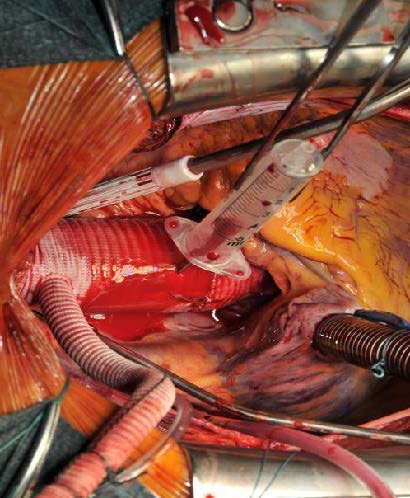

Image 3: The composite graft is then parachuted into the aortic annulus (mechanical valve) or placed in a supra-annular position when a bioprosthetic valve has been used. The sutures are tightened and cut. At this time, the core temperature has usually be brought to 28 or 30°C to proceed with the distal anastomosis at the level of the proximal (open) aortic arch.

Once the annular anastomosis has been performed, the temperature of the patient has usually reached the targeted core temperature of 28 to 30°C. The patient is placed in Trendelenburg position and Pentothal is administered. After the bispectral index has been reduced to zero, the extracorporeal circulation is interrupted. The arterial cannula is pulled out of the ascending aorta. At this time, the cranial part of the ascending aorta is resected and then selective perfusion catheters are placed into both common carotid arteries for antegrade selective cerebral protection. Usually it takes about 30 seconds to 1 minute to start cerebral perfusion. This technique of cerebral perfusion requires a constant flow of about 500 milliliters per minute, with a perfusion pressure not exceeding 60 mmHg. During hypothermic circulatory arrest with cerebral perfusion, the distal anastomosis is constructed at the level of the innominate artery. Usually a Vascutek Anteflow prosthetic graft is used which facilitates recannulation of the patient through the sidearm of the prosthesis, as soon as the distal anastomosis has been performed. Just before re-starting the extracorporeal circulation, the author pulls back the perfusion catheters and looks at the almost completed de-airing of the supra-aortic branches, the aortic arch, and the prosthesis that is clamped just below the sidearm. Control of the hemostasis can be done very easily at this stage around the whole anastomosis.

At this stage, the ascending aorta is de-aired using a needle and the cross-clamp is removed. The patient is still in Trendelenburg position and the de-airing is facilitated with the use of CO2 insufflation in the operating field (Image 7). Epicardial pacemaker electrodes are placed on the ventricle and the right atrium and the patient is weaned from cardio-pulmonary bypass under AAI-stimulation 90/min. as soon as the core temperature has reached 35.5 °C.

Image 7: ;Intraoperative situs at the end of the procedure. The composite graft prosthesis has been anastomosed with the proximal arch – ascending graft. A needle is used for de-airing. The patient is in Trendelenburg position. Left the anteflow side-arm with the arterial cannula for return from CPB.